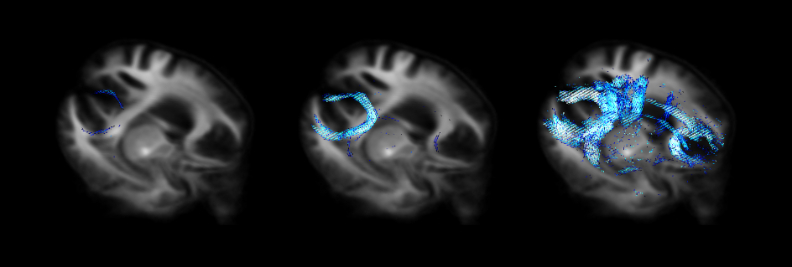

又如,醫學影像原本是失智症及帕金森氏症等神經退化疾病的標準檢測項目,但是只限於排除其他可能病因的出現,無法作為疾病本身的診斷。「健康老化研究中心」運用AI結合高階磁共振造影,可以主動透過影像來診斷,不需增加檢查的時間及費用,更可大幅提升醫師診斷的信心,協助病程分級及病人預後,改善後續的醫療處置。該中心與美國南加大影像遺傳學中心、英國倫敦大學失智症中心等跨國合作,也攜手基隆、林口龜山等地的長照中心,以科技實現健康老化。

長庚大學連結台塑集團資源,跨醫療與製造領域培育AI人才_img_2(圖說:長庚大學運用AI技術所開發之大腦神經纖維追蹤圖譜,協助神經退化性疾病之病程分級及病人預後。)